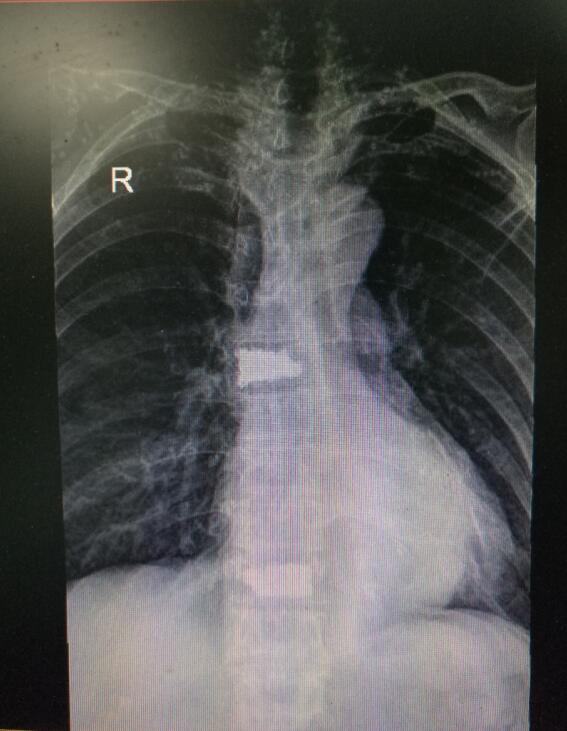

術(shù)后DR(數(shù)字化的x射線)

入院后第四天,由骨傷二科副主任楊陳一、劉永森醫(yī)生、唐國皓醫(yī)生聯(lián)合為患者成功實(shí)施了微創(chuàng)下的經(jīng)皮穿刺椎體后凸成形術(shù)。術(shù)后,患者腰背部疼痛逐漸緩解,術(shù)后第二天即下床活動(dòng)。

“該微創(chuàng)術(shù)式主要針對(duì)中老年患者發(fā)生的胸腰椎壓縮骨折,具有創(chuàng)傷小、恢復(fù)快、術(shù)后第二天即可下床行走等優(yōu)勢,一般患者住院4—5天即可?!碧茋┽t(yī)生表示,考慮到該患者前后兩次骨折均無明顯誘因,背后主要的“元兇”在于其基礎(chǔ)疾病——骨質(zhì)疏松,在治療過程中,除了治療患者的骨折,術(shù)后醫(yī)生還采用院內(nèi)制劑壯筋補(bǔ)骨丸等,積極對(duì)其骨質(zhì)疏松進(jìn)行改善治療,增強(qiáng)其骨密度。經(jīng)過10余天的有效治療,現(xiàn)患者骨折已基本痊愈,骨質(zhì)疏松也得到了一定的改善,于12月12日康復(fù)出院。